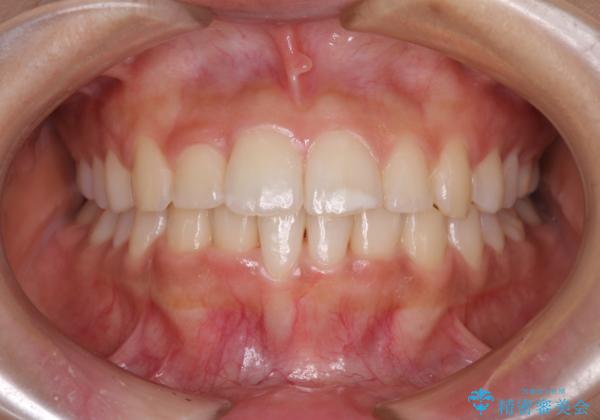

大きなトラブルもなく、順調に歯列が整ったため、僅か9ヶ月で装置を外すことができました。

あまりに短期間であったため、患者様自身も非常に驚いていらっしゃいました。